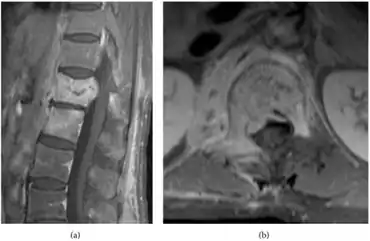

Plain-film radiological orders are necessary for all people displaying symptoms of the disease; this diagnostic approach is often preliminary to other radiological procedures, such as magnetic resonance imaging, computed tomography (CT) scan, fine-needle aspiration biopsy[5]. The initial plain-film X-ray images are scanned for any indication of disc compression between two vertebrae or the degeneration of one or more vertebrae. MRI scans do not expose the person to radiation and are highly sensitive to changes in the size and appearance of the intervertebral discs. If MRI imaging is inconclusive, the high sensitivity to erosions in the vertebrae or intervertebral discs of CT scans may be preferred for their ability to indicate signs of the disease more clearly than MRI. Additional tests may be ordered if such preliminary tests cannot confirm a diagnosis, for example, needle biopsies may be needed to take samples of bone surrounding the disc space where the infection is thought to live[12][13][5]

CT scan

MRI